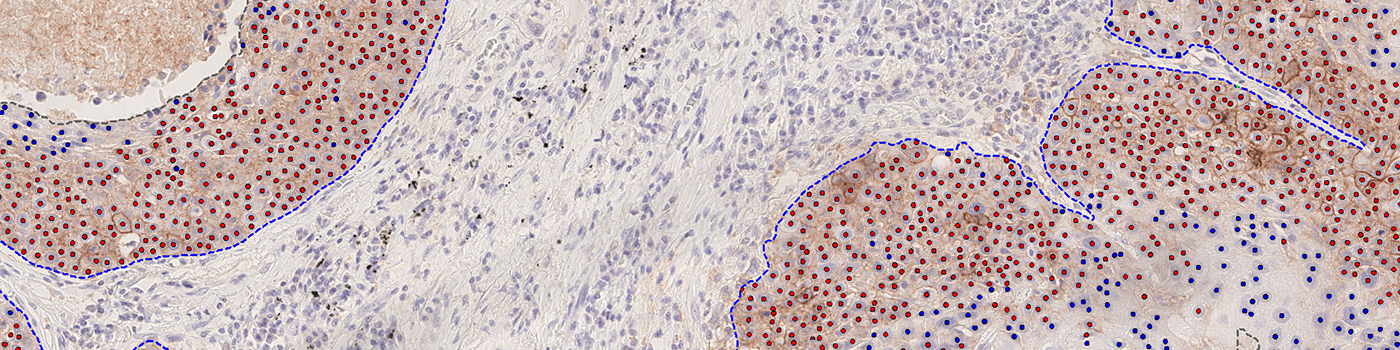

Our PD-L1 solution is fully automated and does not require manual input during analysis. The solution consists of four automated analysis steps. Once started, it automatically separates the patient tissue from control tissues and robustly identifies invasive cancer areas in the sample. Tumor cells are counted based on their PD-L1 expression and the resulting Tumor Proportion Score (TPS) for the whole tumor area is calculated.

Total Tumor Nuclei (#): The number of tumor nuclei within all ROIs

TPS (%): The PD-L1 Tumor Proportion Score (TPS)